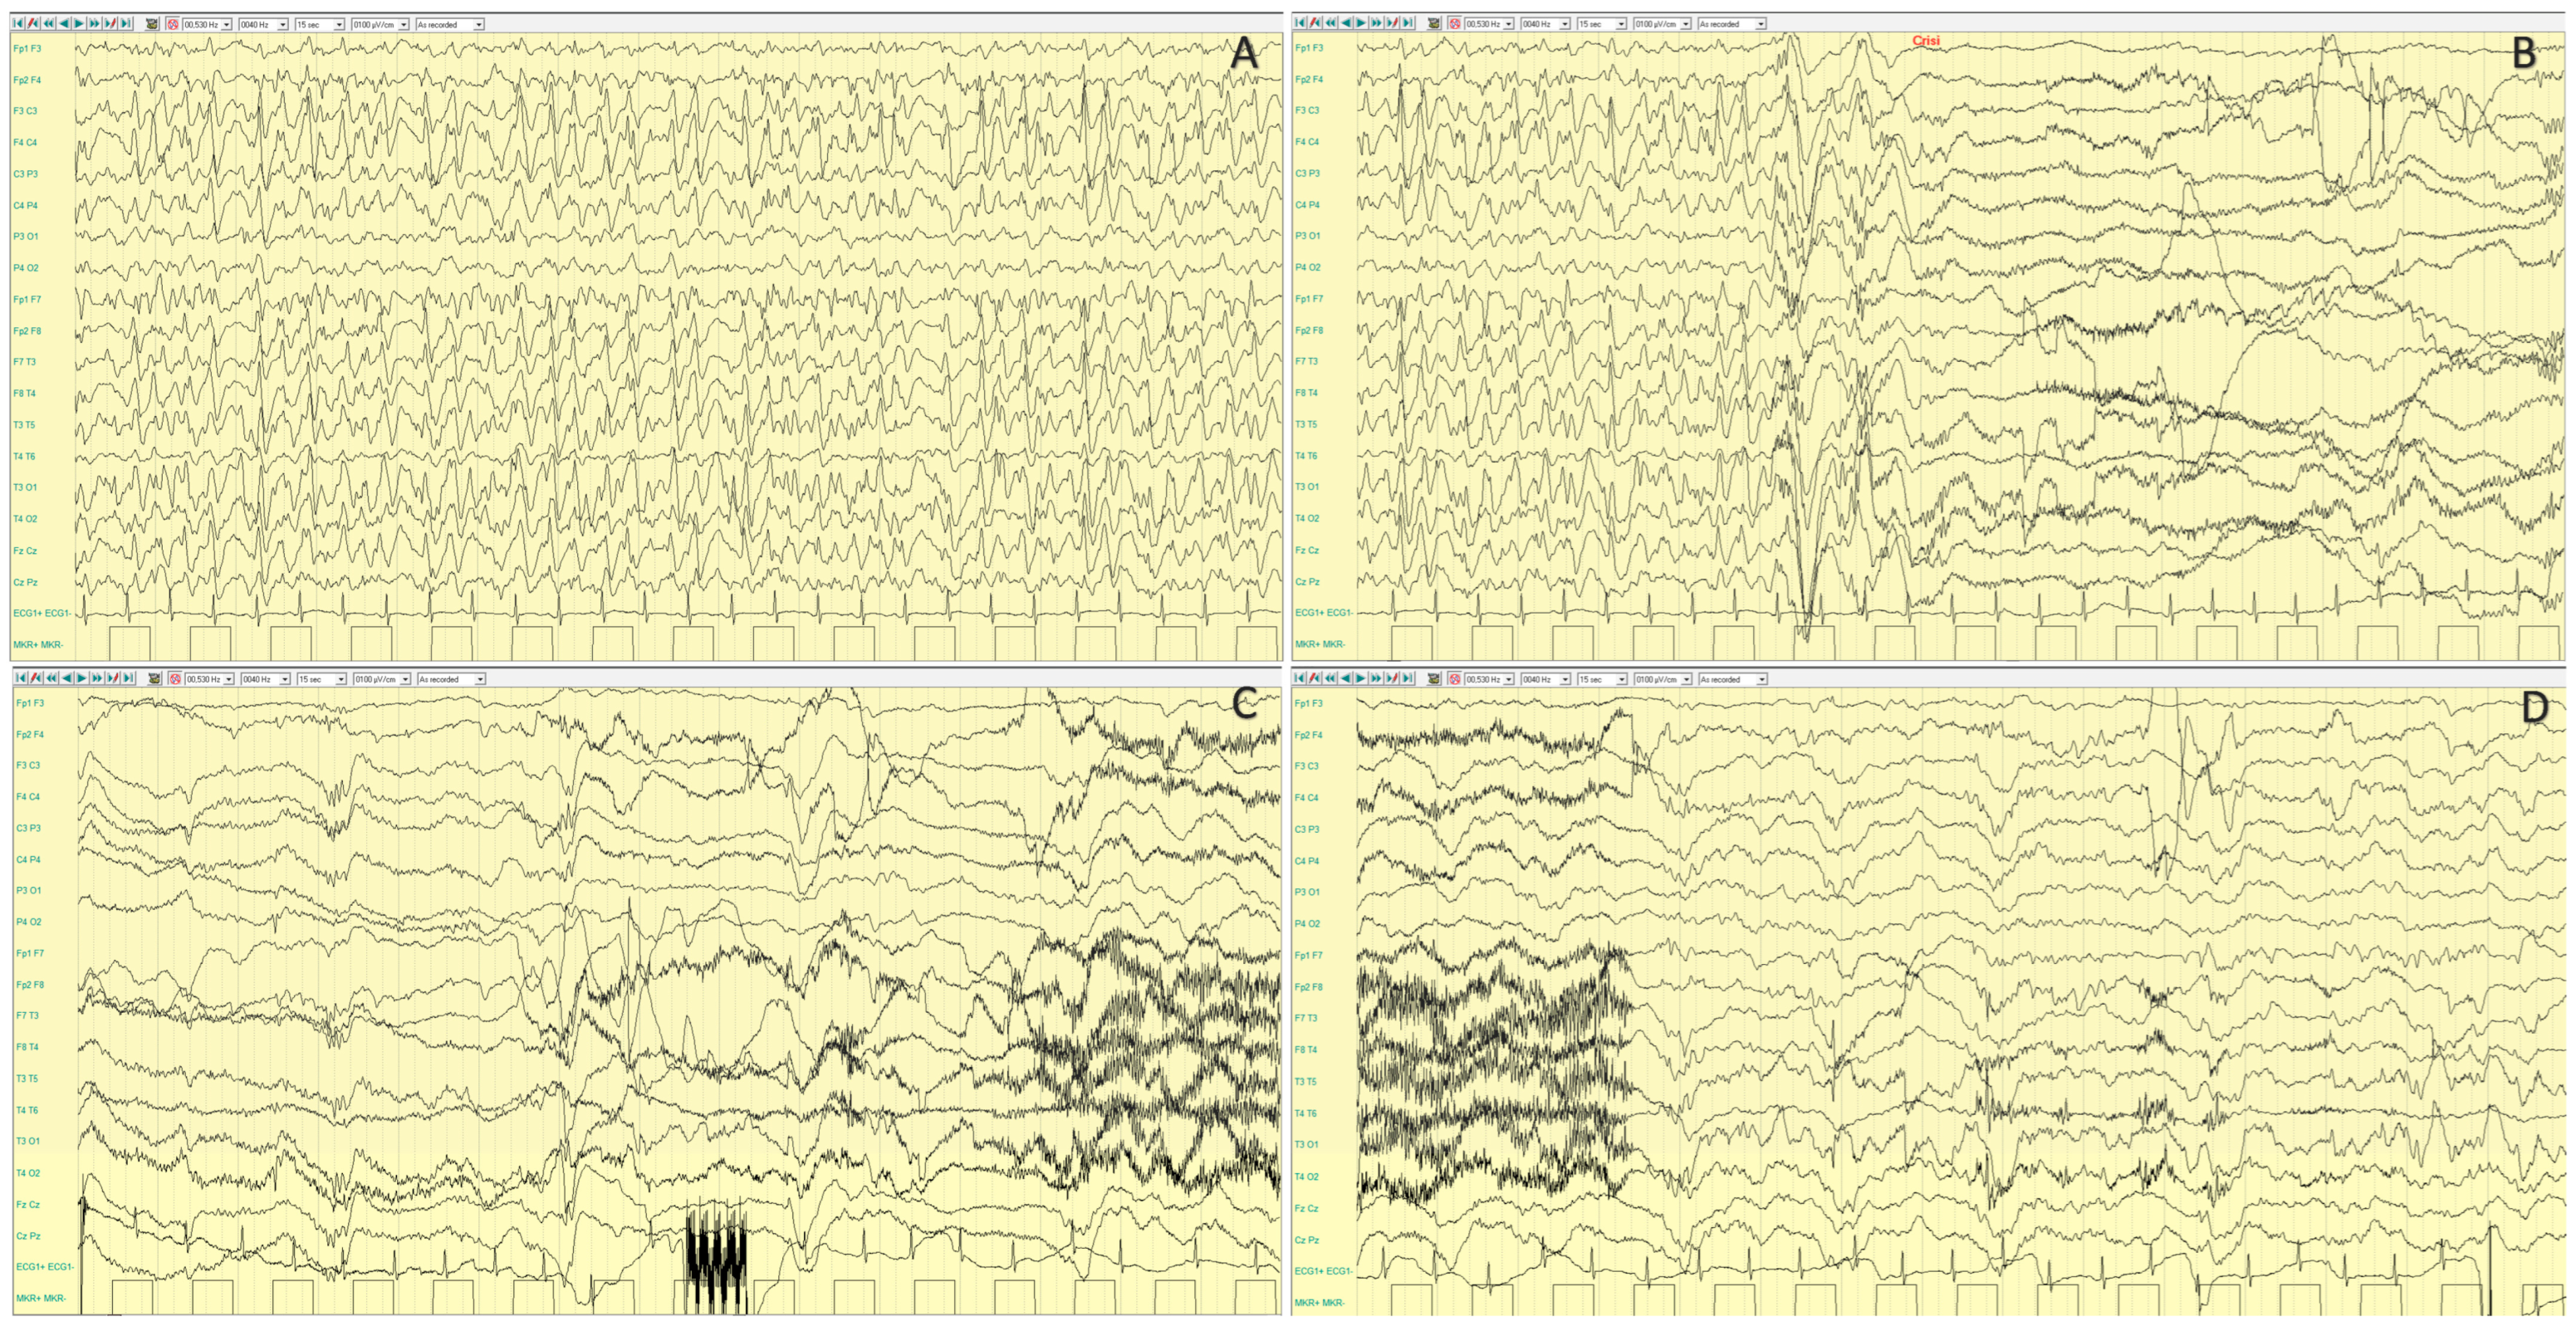

4.2.2. Epileptic Phenotypes